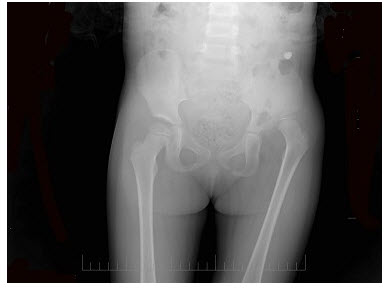

213、单项选择题

患者女,6岁,左下肢跛行三年,直立时臀部后耸,结合骨盆平片,正确的诊断是()

A.左髋内翻畸形

B.左髋结核

C.左先天性髋关节脱位

D.左股骨头缺血坏死

E.左髋关节炎